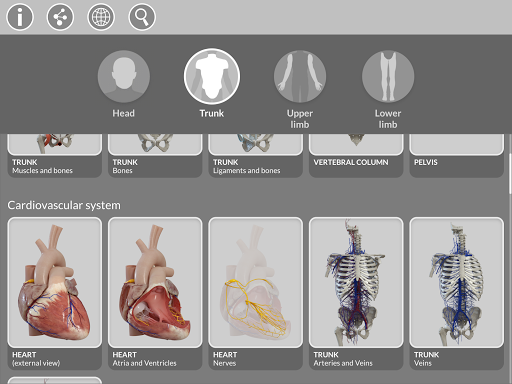

Việc phân chia theo vùng và chế độ xem được xác định trước giúp quan sát và nghiên cứu các bộ phận hoặc nhóm hệ thống riêng lẻ và mối quan hệ giữa các cơ quan khác nhau.

MÔ HÌNH GIẢI PHẪU 3D

• Hệ thống cơ xương

• Hệ thống tim mạch

• Hệ thống thần kinh

• Hệ thống hô hấp

• Hệ thống tiêu hóa • Hệ thống tiết niệu sinh

dục (nam và nữ)

• Hệ thống nội tiết • Hệ thống

bạch huyết

• Hệ thống mắt và tai